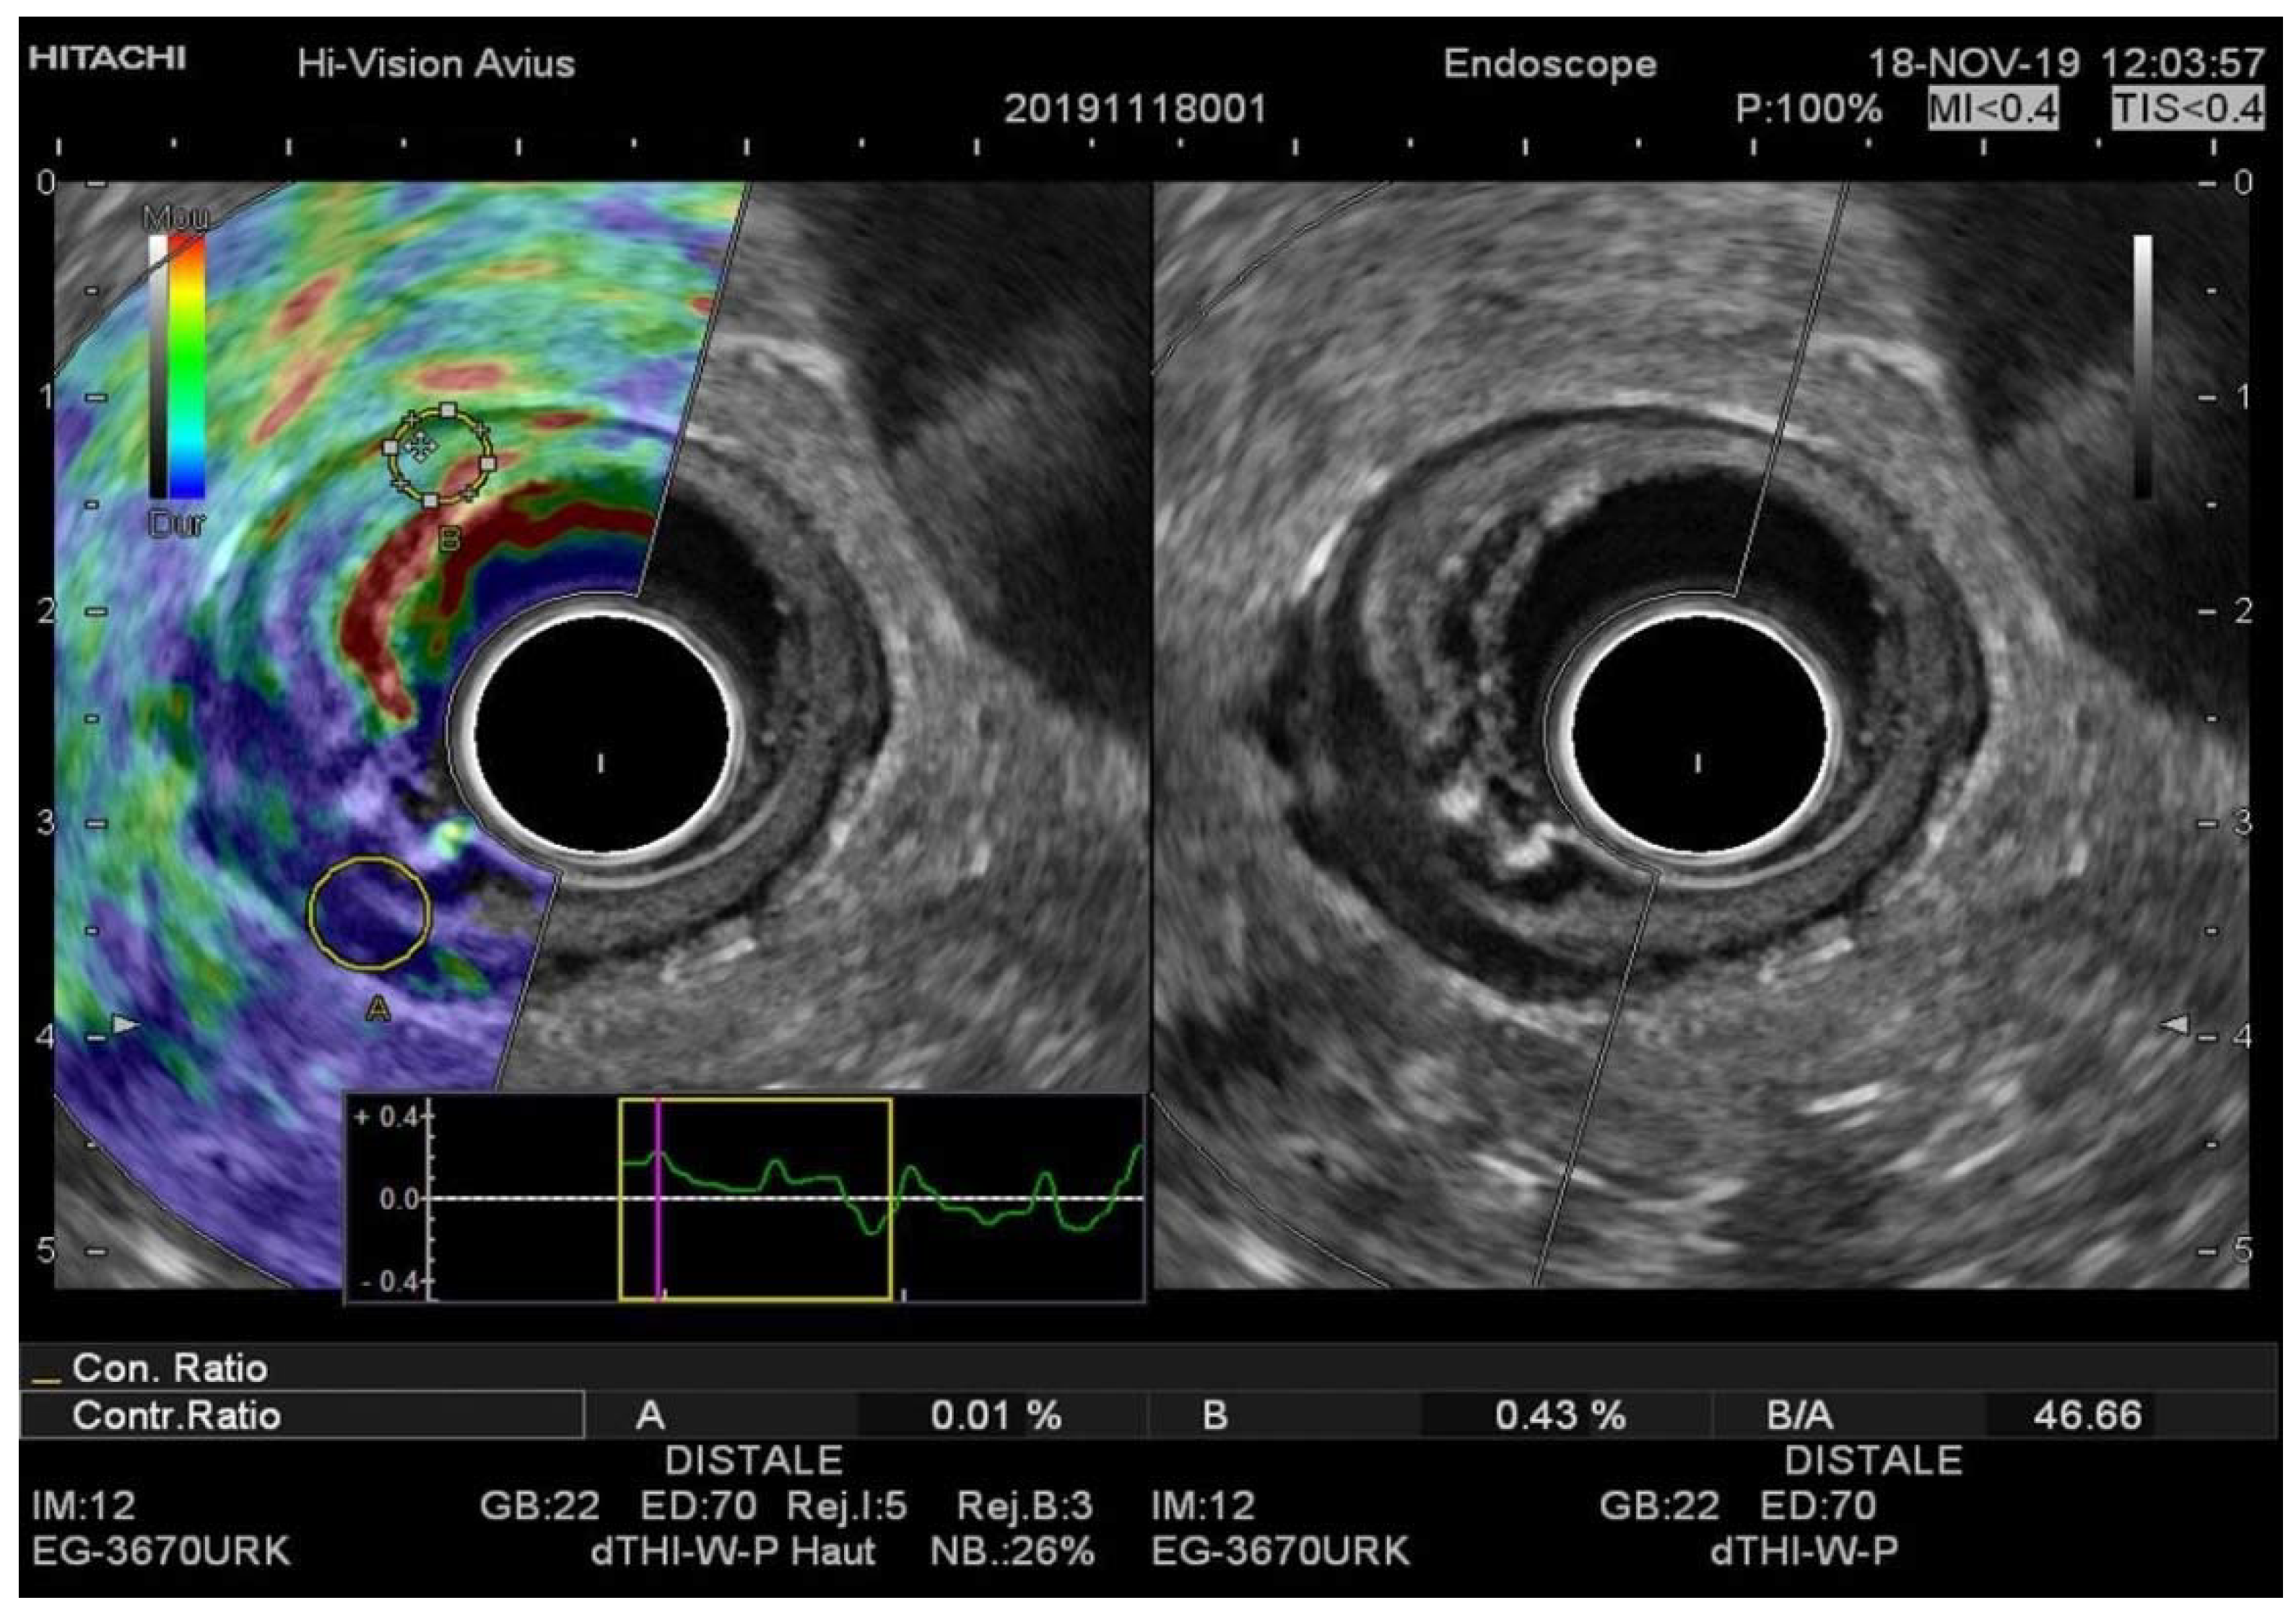

Figure 3. (A) EUS-RTE aspect in a 67-year-old female with pT3 rectal cancer. (B) EUS aspect of the same tumor. The tumor was classified as T3 with the cutoff value strain ratio (B/A) of 46.66. T3 was confirmed by histopathologic examination after surgical resection. RTE, real-time elastography.